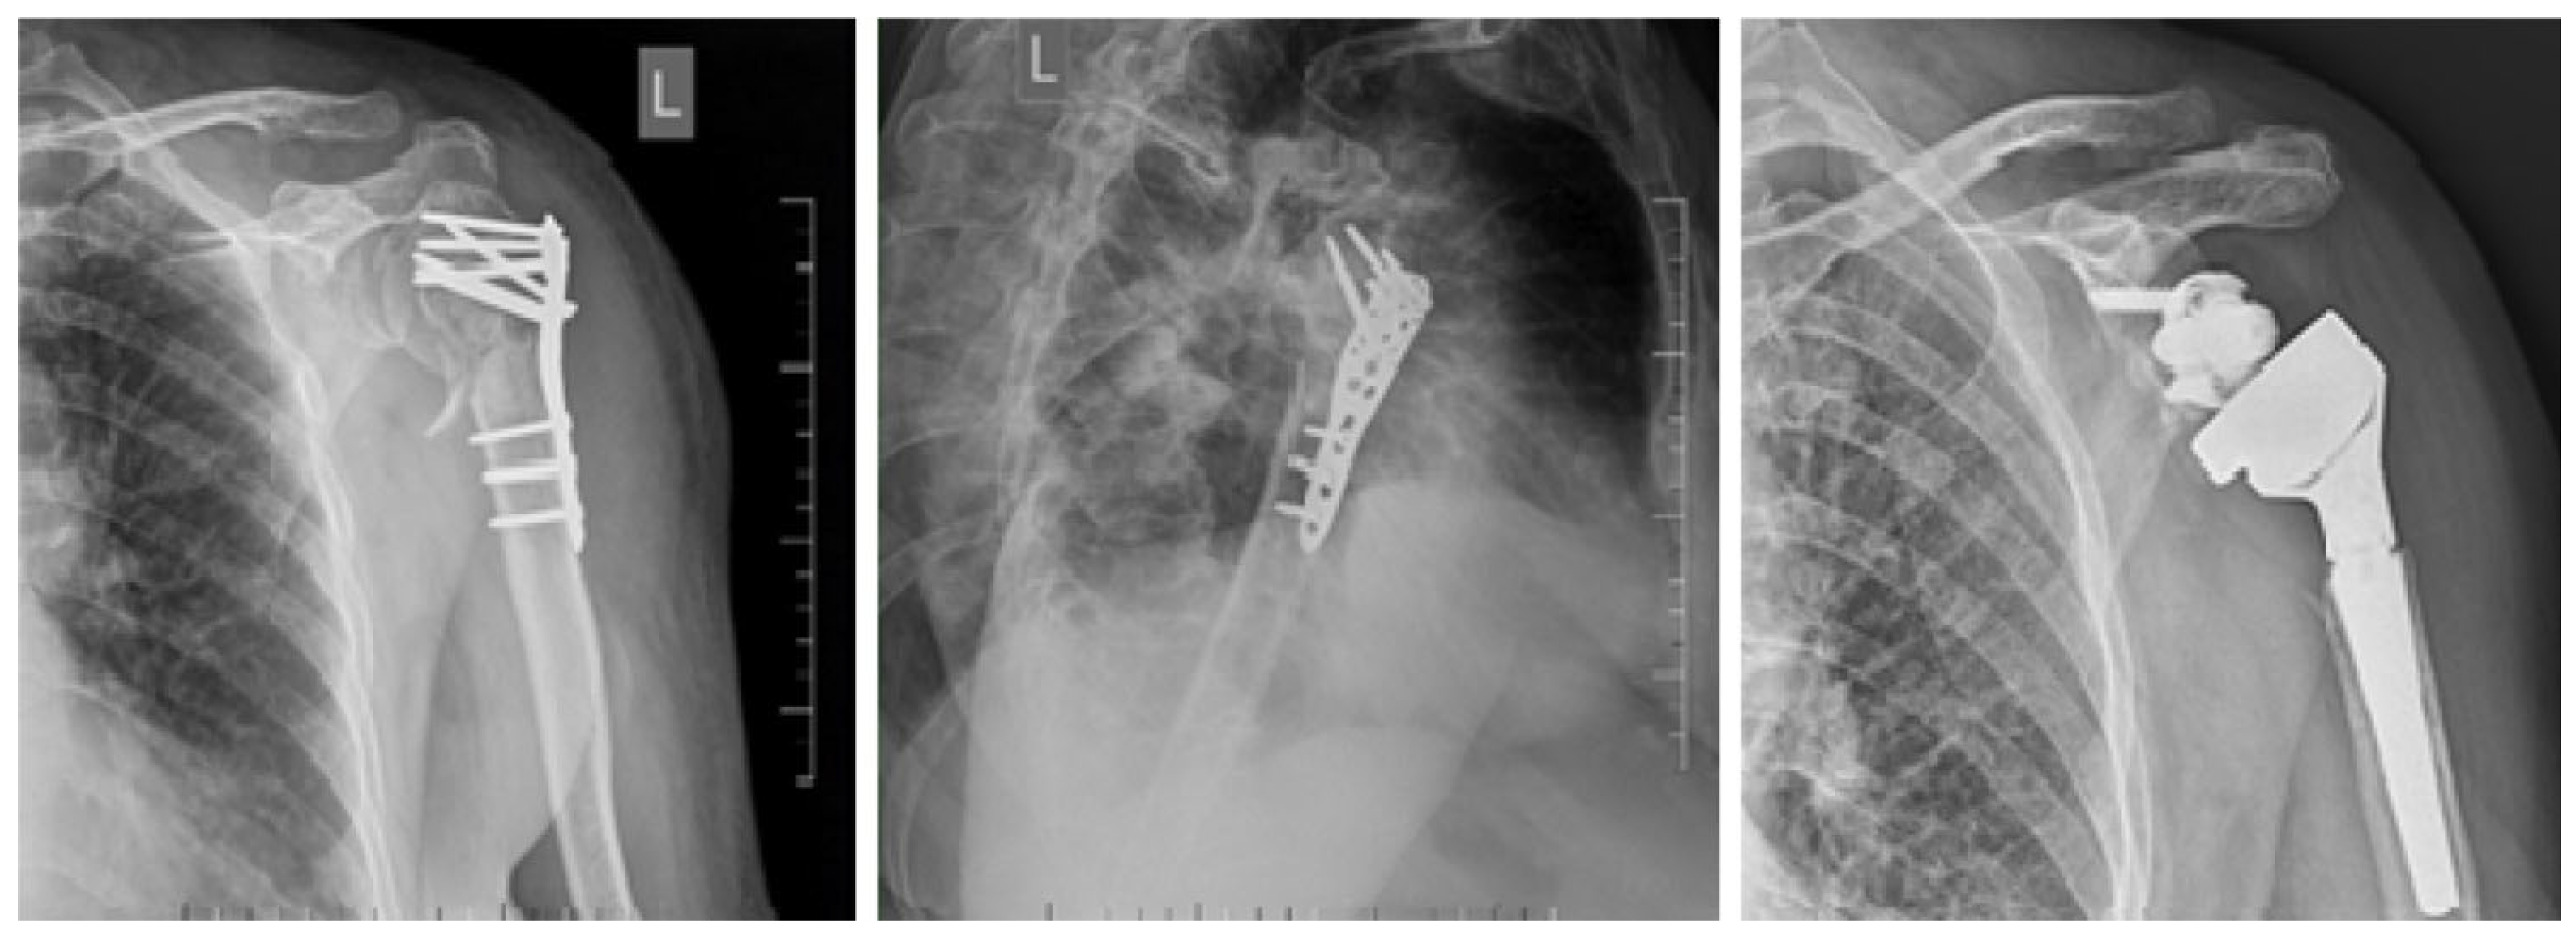

2. Materials and Methods